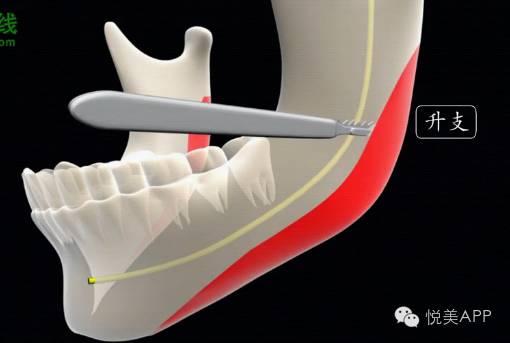

人体的下颌骨中有一个非常重要的解剖结构,叫做下齿槽神经血管,它在哪里呢?它就在下颌骨的里面沿线走~

曲面断层中也能看到——

所以在截骨的时候,一定不能切到神经血管

▼▼

切得太高就有可能把下齿槽的神经血管给破坏

一旦神经血管被破坏,

一个是出现大出血,

一个会导致下唇局部的麻木